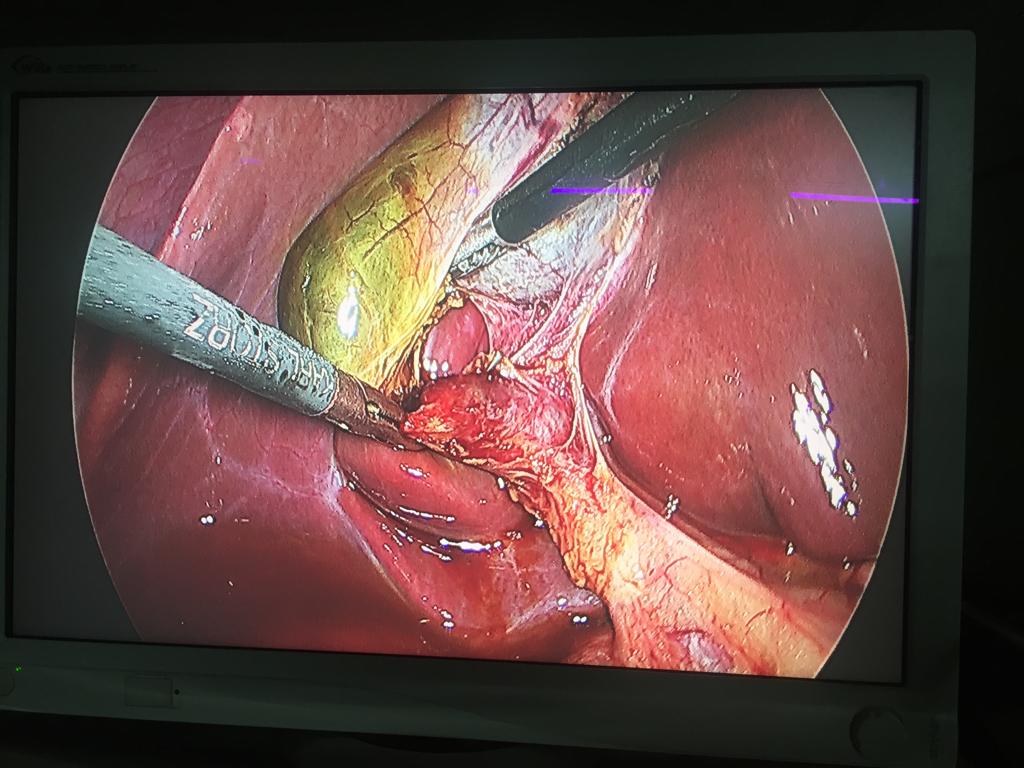

Acute Cholecystis, Mucocele Gallbladder with big stone at the neck. Completely done Laparoscopically